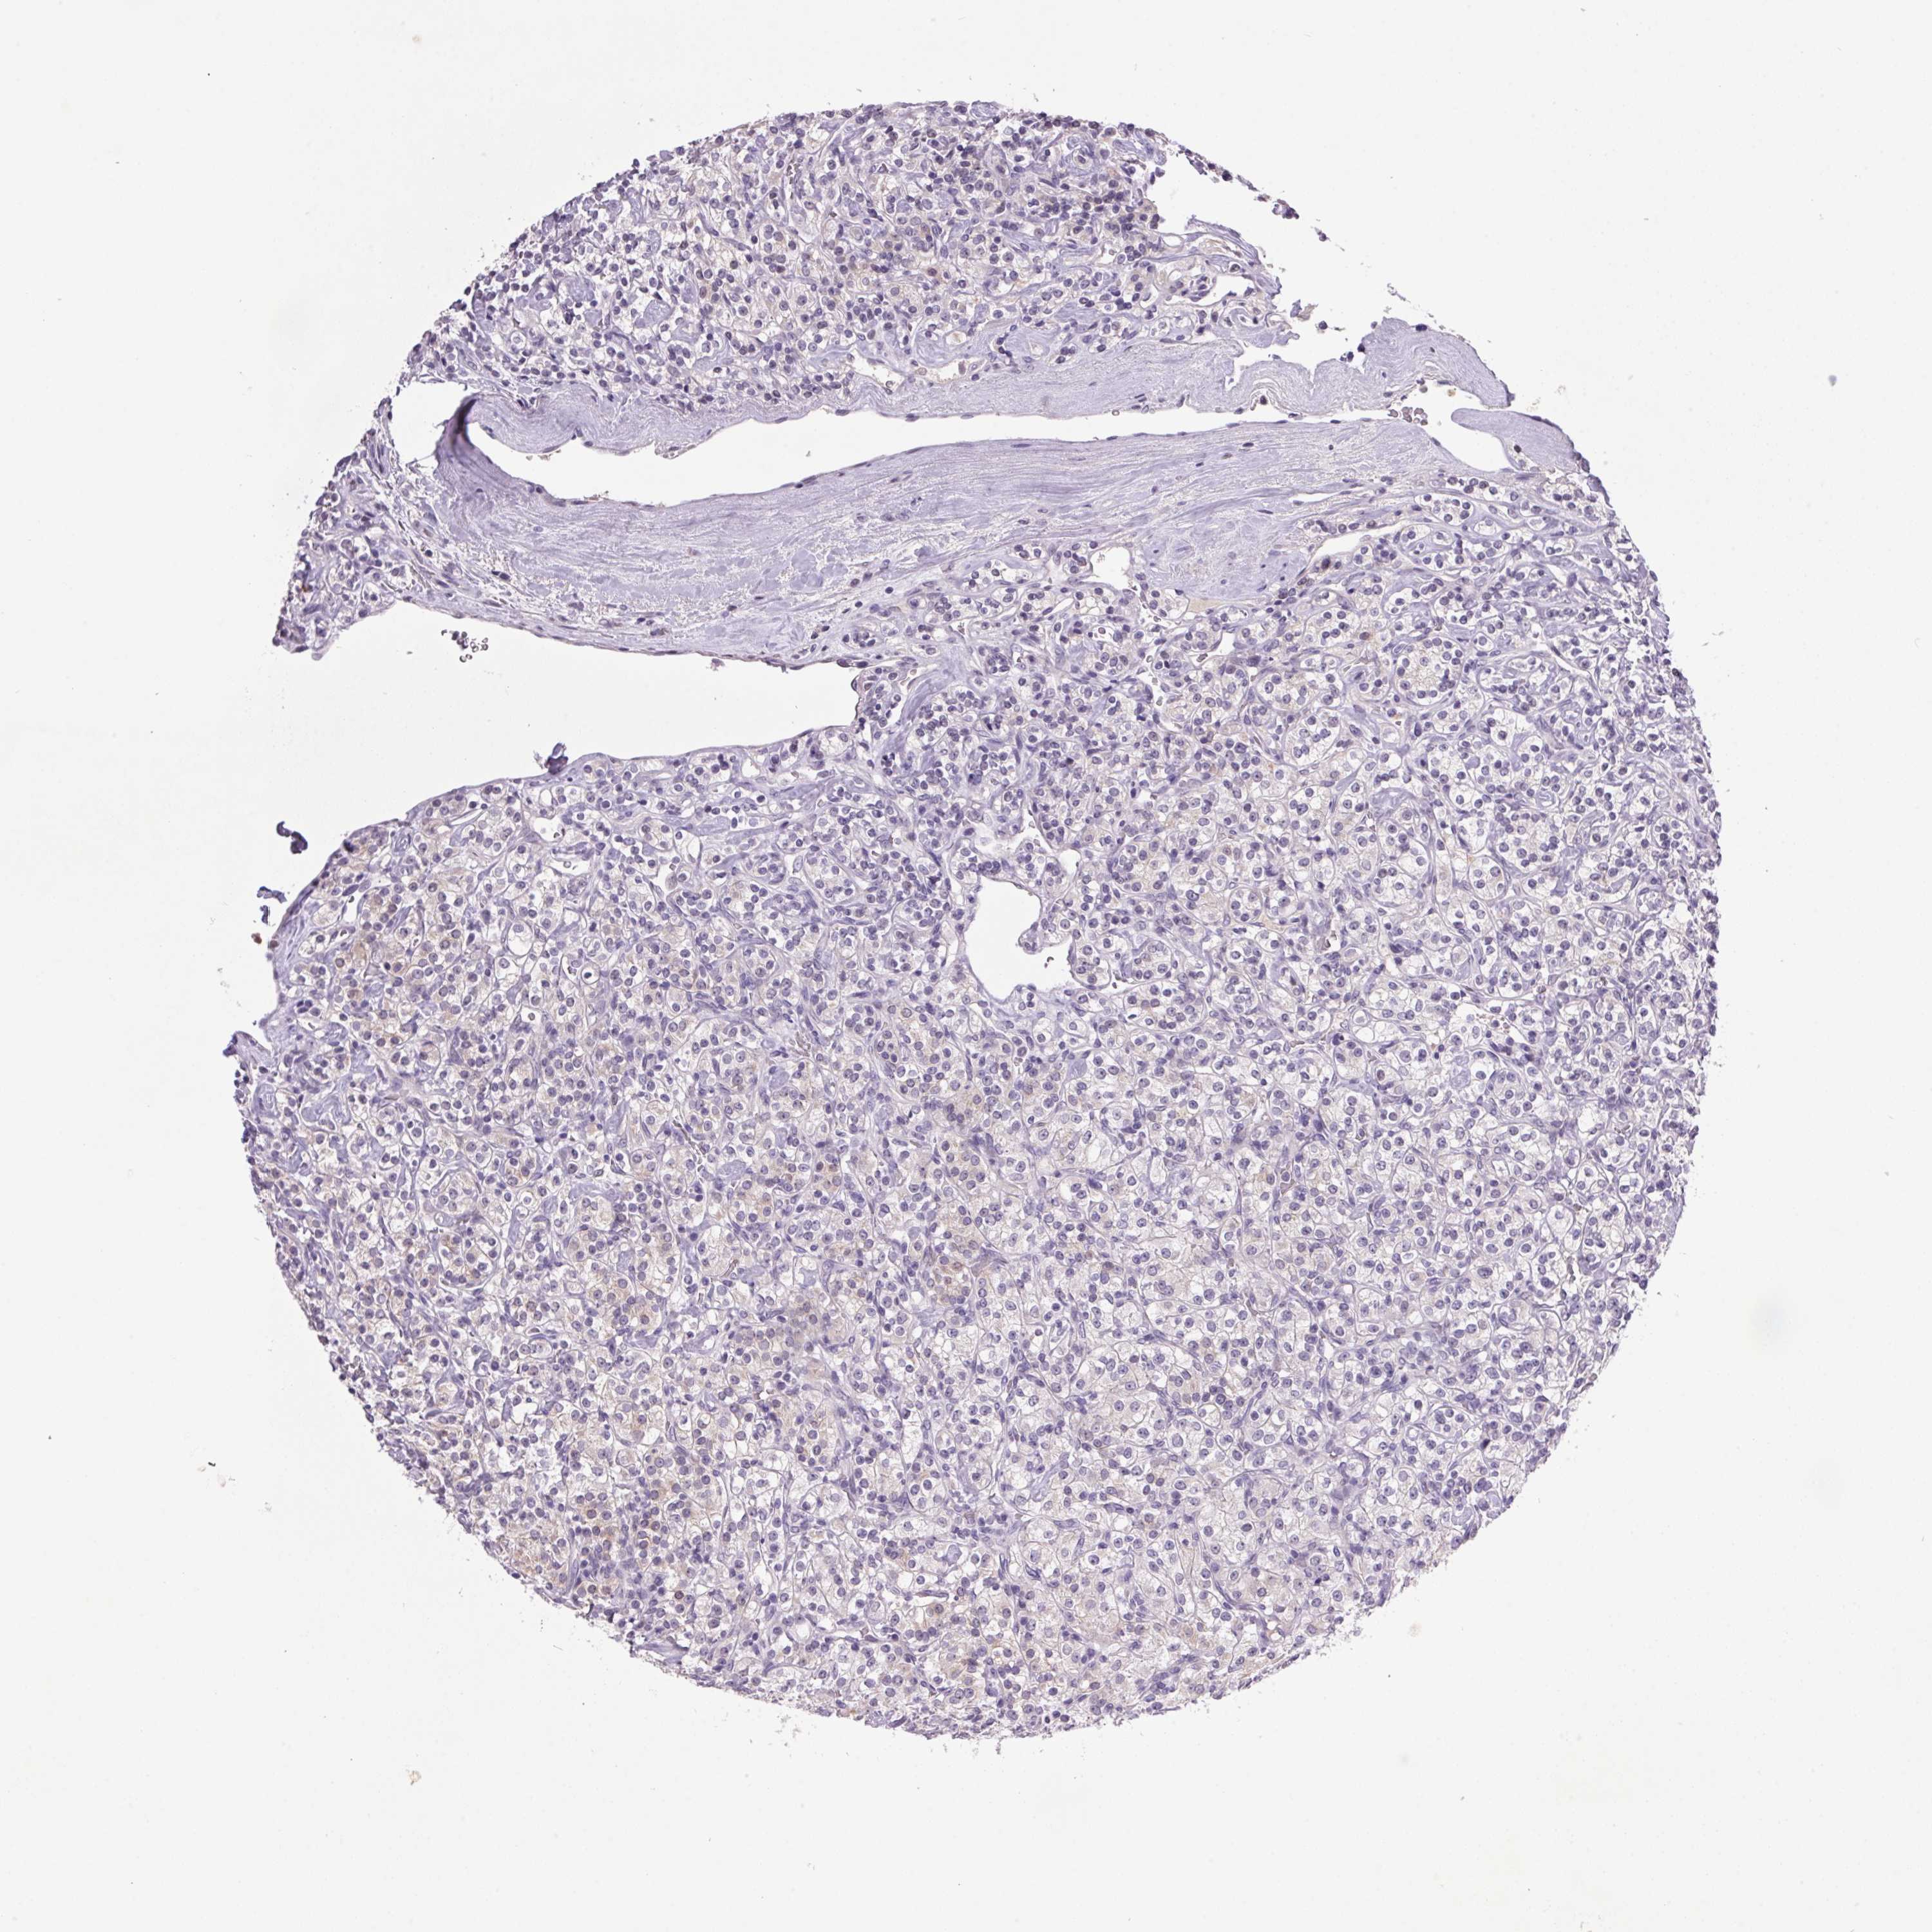

TCGA RNA samplesi

RNA-seq data is reported as average FPKM (number Fragments Per Kilobase of exon per Million reads), generated by the The Cancer Genome Atlas (TCGA) .

Normal distribution across the dataset is visualized with box plots, shown as median and 25th and 75th percentiles. Points are displayed as outliers if they are above or below 1.5 times the interquartile range. FPKM values of the individual samples are presented next to the box plot.

Average pTPM 0.1

Number of samples 282